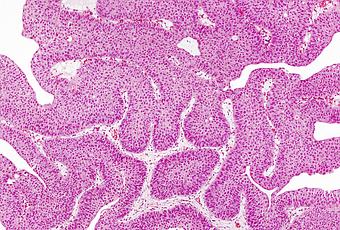

Le cancer urothélial est le type le plus courant de cancer de la vessie (90% des cas). Ce cancer peut se développer dans le bassin rénal (où l'urine s'accumule à l'intérieur du rein), dans l'uretère (tube qui relie les reins à la vessie) et l'urètre. L'un des traitements les plus largement utilisés est la chimiothérapie qui agit en ciblant toutes les cellules du corps, agissant avec succès sur les cellules cancéreuses, mais affecte également les cellules non cancéreuses, avec des effets secondaires.